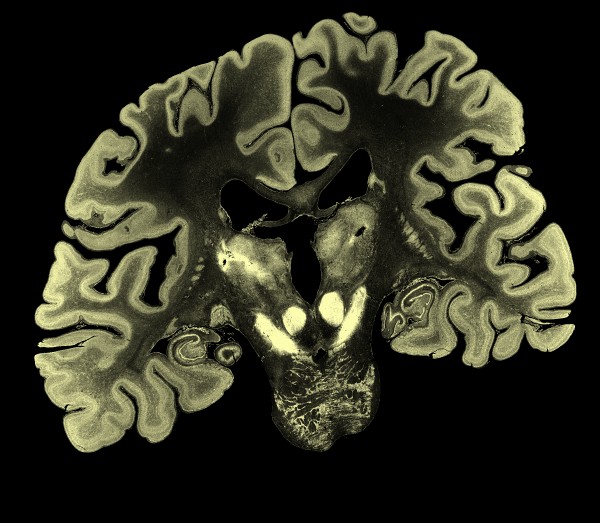

| Preserved human brain, 65-year old female.

| Slices 5 times thinner than sheet of paper.

- Show Big Brain 400 um volume surface rendered.

- Show ortho-plane slices of 100 um or 400 um brain.

- Show 20 um single plane zoomed in to pixel size.